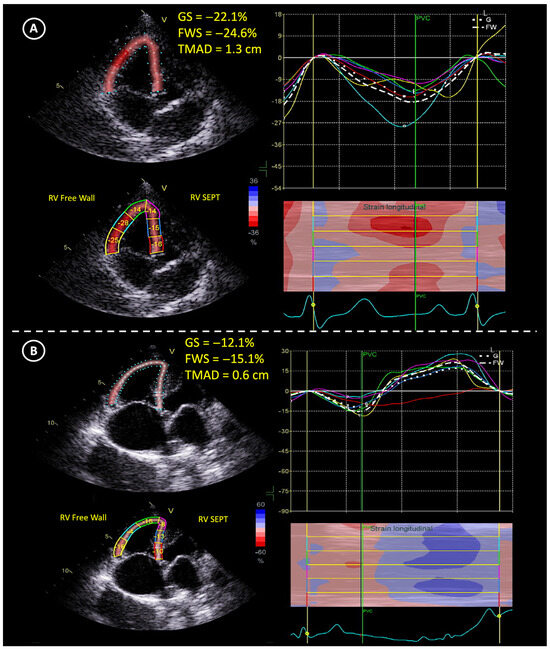

| TMAD (cm) | 1.1 ± 0.2 | 1.0 ± 0.2 | 0.7 ± 0.3 | 0.00 (1.27) 6 |

| GS (%) | −25.6 ± 4.9 | −25.2 ± 4.0 | −15.8 ± 4.4 | 0.00 (1.58) 6 |

| FWS (%) | −26.7 ± 4.7 | −26.2 ± 3.5 | −16.9 ± 5.0 | 0.00 (1.6) 6 |